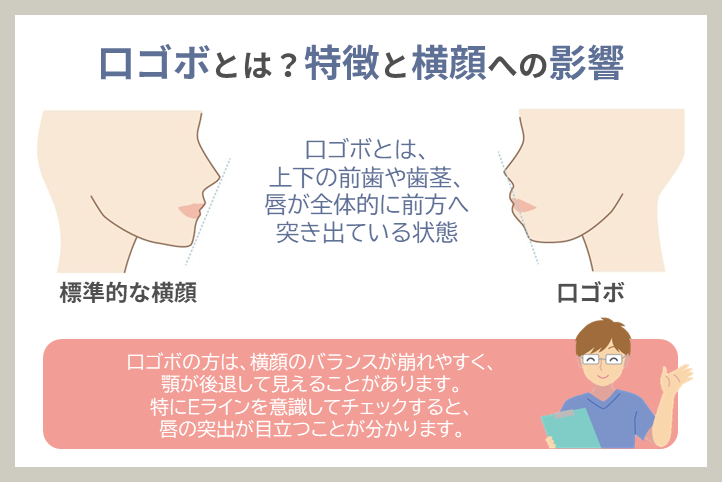

口ゴボとは?特徴と横顔への影響

口ゴボとは、上下の前歯や歯茎、唇が全体的に前方へ突き出ている状態を指します。正式には「上下顎前突(じょうげがくぜんとつ)」と呼ばれ、骨格のズレや歯並びの問題によって引き起こされます。

口ゴボの特徴

- 唇が閉じにくく、リラックスした状態でも口が少し開いてしまう

- 横顔を見たときにEライン(鼻・唇・顎を結ぶライン)よりも唇が前に出ている

- 正面から見ると口元がもっこりして見える

- 口角が下がりやすく、不機嫌な印象を与えることがある

横顔への影響

口ゴボの方は、横顔のバランスが崩れやすく、顎が後退して見えることがあります。特にEラインを意識してチェックすると、唇の突出が目立つことが分かります。